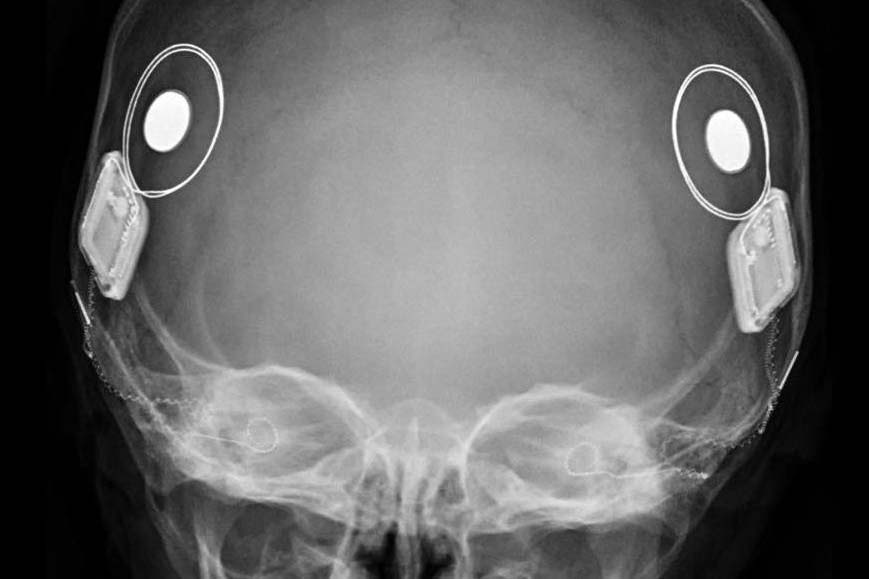

Conhecido popularmente como "ouvido biônico", o implante coclear é um dispositivo eletrônico de alta tecnologia inserido através de cirurgia. Diferente dos aparelhos auditivos convencionais, que apenas amplificam o som, o implante estimula diretamente o nervo auditivo.

O dispositivo conta com uma parte interna, que é colocada cirurgicamente dentro da cóclea (caracol da audição) e uma parte externa (que fica visível na parte posterior da cabeça) que é formada por um processador que capta o som ambiente. As duas partes são conectadas por um ímã, sendo que a externa deve ser retirada para tomar banho e dormir, e a bateria precisa ser carregada.